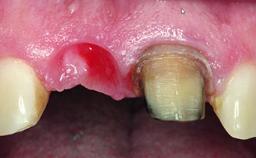

A healthy 37-year-old female patient was referred for a consultation on the replacement of missing tooth 21 with an implant-supported restoration. She stated that several years previously the tooth had been traumatically avulsed following a motor vehicle accident. The tooth was replaced with a three-unit fixed partial denture (FPD) immediately afterwards. Over time, she became disillusioned with the FPD and looked for a different option, including orthodontic therapy. She presented still in her orthodontic appliances, with the pontic sectioned free from the FPD but attached to the archwire. Her orthodontist felt that orthodontic treatment had been successfully completed, but nevertheless referred her before removing the appliances in case adjustments were necessary.

Bone Volume Horizontally and vertically sufficient Horizontally deficient Deficient vertically or deficient vertically AND horizontally

Bone Volume Deficient horizontally, allowing simultaneous augumentation